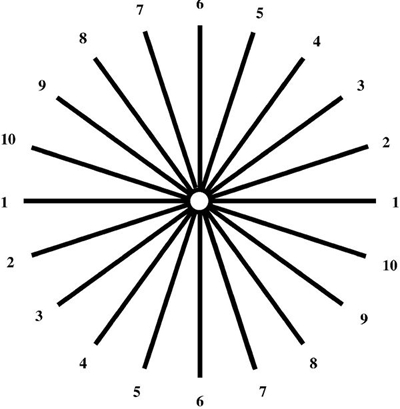

A:判斷自己有沒有散光,最簡單的方法是使用散光表來測試。散光表是一種簡單、方便的方法,但是它的準確度不是特別精確。在配鏡的情況下一般再用裂隙法,或者是交叉圓柱鏡法來精調散光的度數。散光表在網上可以看到,它類似於鐘錶的盤面,有12個數字。各個鏡線……